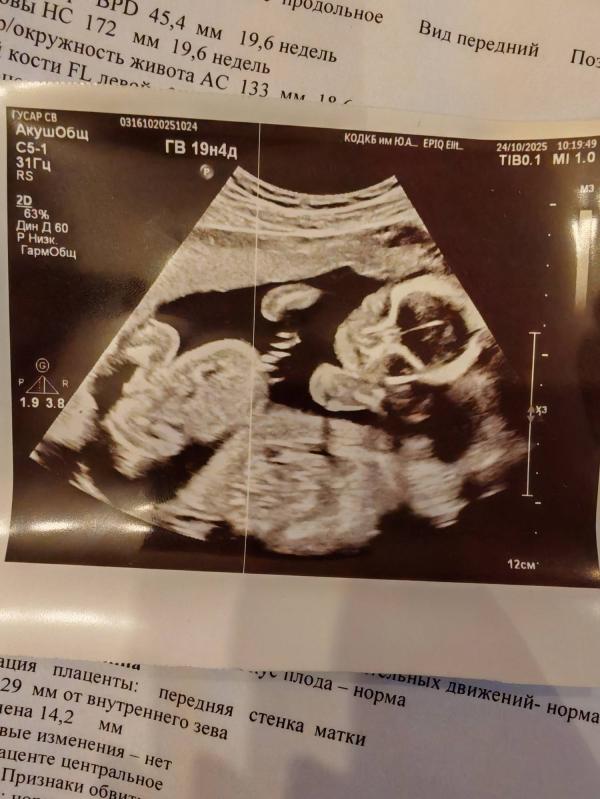

Девочки, мне кажется или сразу видно что мальчик? 😄

Я тоже сразу увидела, но не уверена вдруг по изи как то по другому 🍆выглядит у маленьких 😂😂😂

Да, это сестры мужа фото, делала 2 скрининг и за то что они скажут ей пол ребёнка попросили 800р, а у неё с собой денег не было и телефон сел